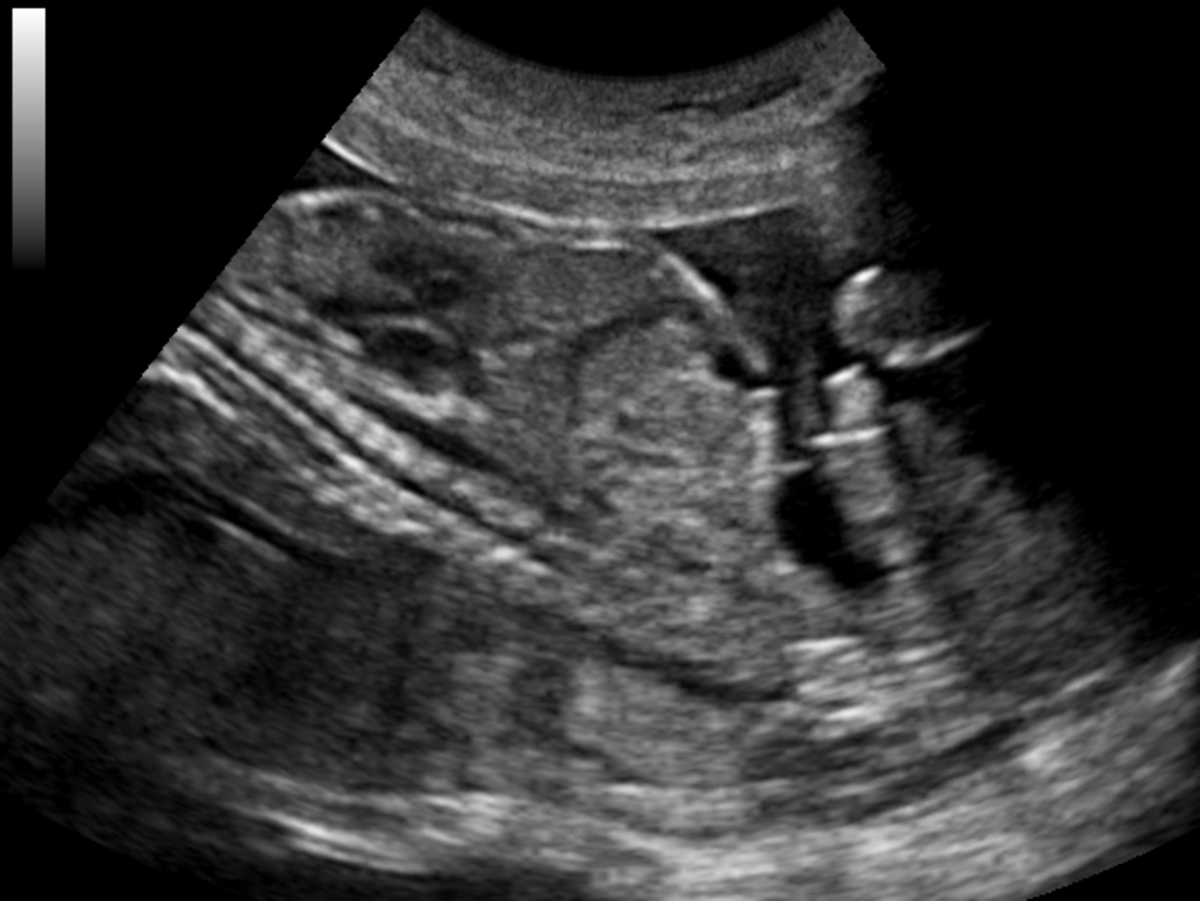

From ar.inspiredpencil.com

Gallbladder Ultrasound Cancer How To Reduce Acoustic Noise Ultrasound To reduce speckle noise, ultrasound compounding techniques have been widely investigated. To enhance speckle noise elimination, we propose a novel algorithm using the characteristics of speckle noise and filtering methods based on speckle reducing anisotropic. Usually, medical ultrasound images are affected by the mixed noise, which is the combination of speckle noise and gaussian. Thus, it is possible to improve. How To Reduce Acoustic Noise Ultrasound.